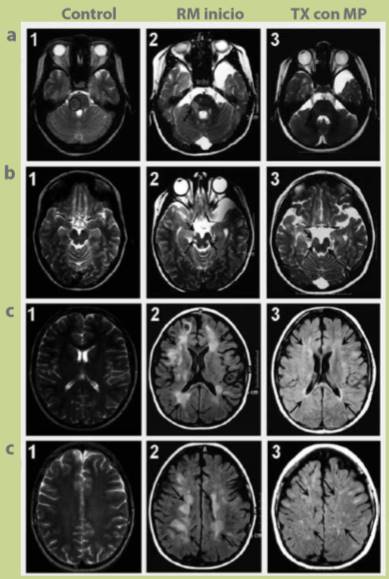

En las valoraciones por imagen de resonancia magnética a las pacientes durante el tratamiento, se observó que al inicio presentaban grandes zonas de desmielinización, y al año de tratamiento con MP desaparecían pero no en su totalidad (figuras a1, a2 y a3), a los 3 y 5 años de tratamiento ya no se visualizaban las zonas de desmielinización en la sustancia blanca (figuras b1, b2, b3, c1, c2 y c3). A 10 años de tratamiento las lesiones de la sustancia blanca y gris cercanas a la corona radiada se han recuperado y la barrera hematoencefálica se encuentra íntegra, con una mínima actividad en sitios de la sustancia gris (figuras a1, a2 y a3).

Figura 1 a1) Se muestran imágenes de cortes axiales de resonancia magnética en ponderación T2, de la región de la protuberancia y pedúnculo cerebeloso derecho. a2) Inicio del tratamiento; la imagen muestra lesiones con zonas grandes de desmielinización en la protuberancia y zonas periventriculares. a3) Imagen tomada un año después del tratamiento con metilprednisona; se observa que las lesiones tienden a desaparecer casi en su totalidad. b1) Se muestran cortes axiales de la región mesencefálica. b2) Al inicio de tratamiento presentaba lesiones hiperintensas en la zona peduncular derecha y tegmento del mismo lado, así como lesión tegmental izquierda. b3) Imagen tomada a los 3 años de tratamiento; se puede observar que en el mesencéfalo en las zonas antes descritas ya no se manifiesta lesión. c1) Se muestran cortes axiales de resonancia magnética en ponderación FLAIR, en región del núcleo caudado. c2) Al inicio de tratamiento muestra lesiones grandes hiperintensas de la sustancia blanca que van desde el lóbulo frontal hasta el lóbulo occipital y de predominio derecho. c3) Resonancia magnética a los 5 años de tratamiento se muestra una clara mejoría y recuperación de la barrera hematoencefálica. d1) Se presentan cortes axiales de resonancia magnética en ponderación FLAIR, región de la corona radiada. d2) Imagen de inicio de tratamiento se aprecian lesiones hiperintensas y grandes placas de desmielinización en la corona radiada, de predominio derecho. d3) Imagen tomada a los 10 años de tratamiento, podemos observar que se aprecia solo un pequeño número de lesiones hacia la sustancia gris y las lesiones de la sustancia blanca han desaparecido.

Con el seguimiento, durante un largo periodo, de los resultados anteriores de RM principalmente en las ponderaciones T2 y FLAIR, por lo tanto, estudios de seguimiento en tiempo y espacio (criterios de MacDonald, 2010), mostramos que la barrera hematoencefálica mejora con los bolos de MP, debido a la exposición crónica y regular a éstos con dosis bajas e intervalos cada vez más amplios. Este argumento tiene fundamento al saber que al atenuar el sistema inmune de manera regular, aun cuando el paciente no tenga recaídas, logramos la estabilización de cascadas y factores proinflamatorios y con ello se da un menor índice de recaídas y un menor daño a largo plazo (principalmente cognitivo), lo que es muy válido para los pacientes donde la causa es la activación del sistema inmune; también vale la pena mencionar que las imágenes a 5 y 10 años no presentan atrofia corticosubcortical con espacio subaracnoideo conservado de manera adecuada, lo cual también es consistente con lo observado de manera perceptiva, el número de recaídas en nuestros pacientes es mínimo y no se presenta discapacidad, pues se encuentran efectuando actividades de la vida diaria.